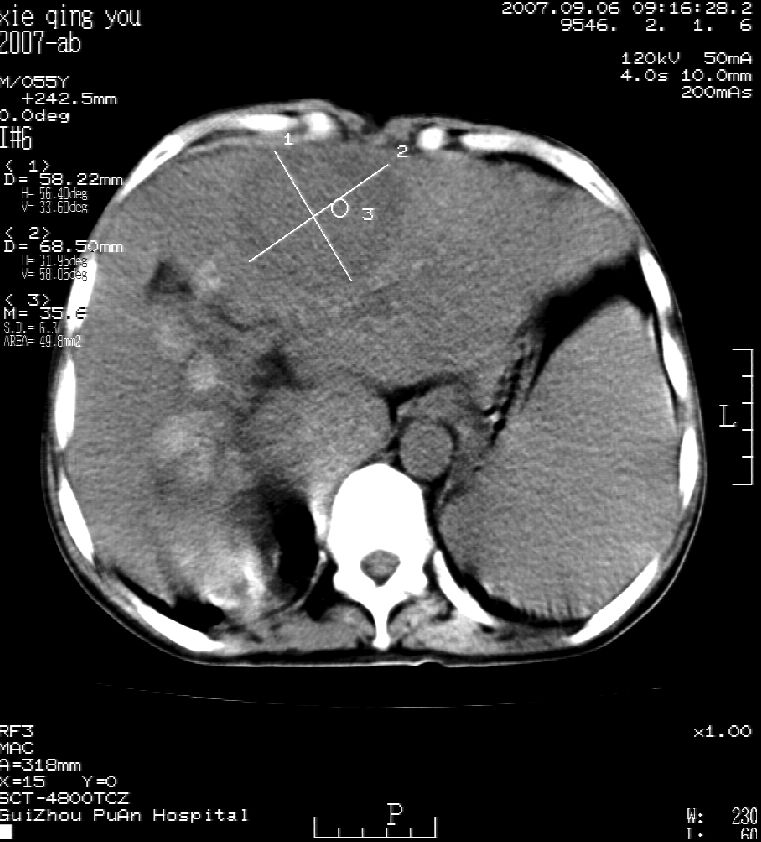

2007年9月片

这个病灶很有意思,怎么可能没有了呢?我考虑当时很可能是肝脏脓肿(b超示囊肿是有可能误诊的,因为影像表现都是低回声吗?),现在脓肿吸收了,肝脏萎缩,肝裂增宽了.别的肝叶代偿增大,不过现在左内叶的确有个占位,肝内多发结石,脾脏比以前大,不排除有肝硬化可能.建议增强扫描给于定性!!!!

肝硬化\\脾大,肝左叶肝癌可能性大,建议增强扫描.肝内胆管多发性结石.

1, 肝硬化,脾大;2,肝左叶肝癌可能性大,建议增强扫描.3,肝内胆管多发性结石.

考虑肝内胆管多发结石引起的肝内局部炎症,这样可以解释2005年肝右叶病灶的吸收和左叶新病灶.